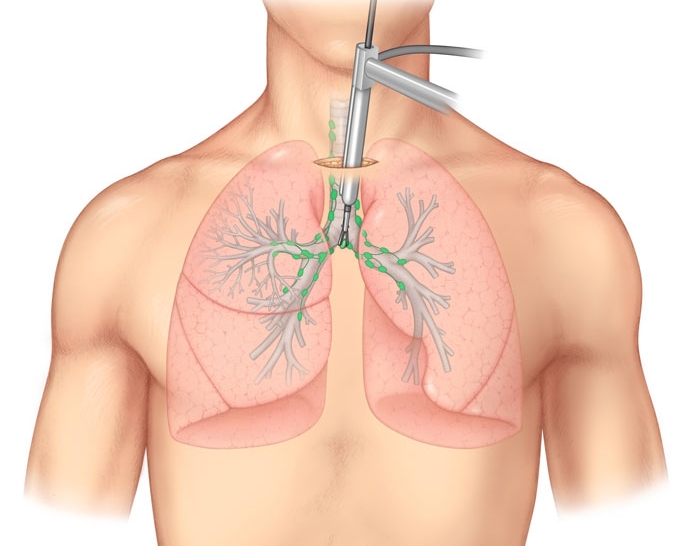

Фотографии и информация о бронхоскопии при туберкулезе